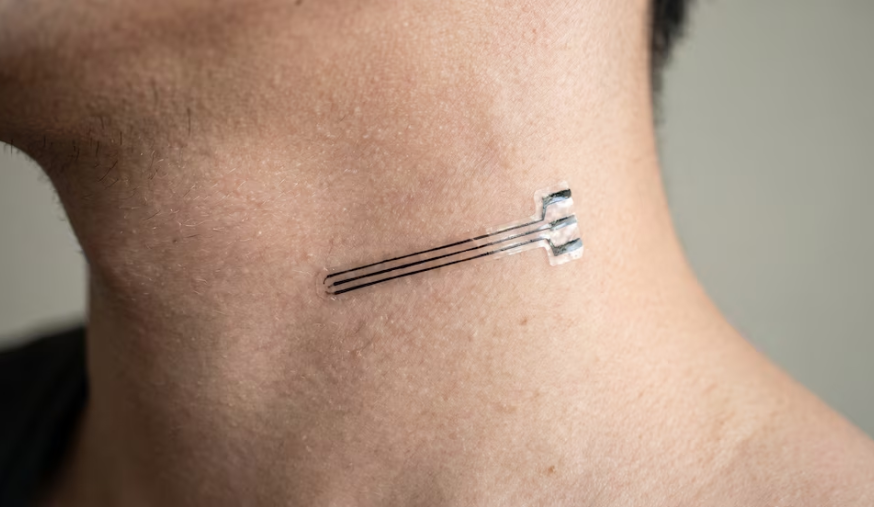

Təzyiq xəstələri üçün yeni ümid - "CaroFlex" implantı yaradıldı

28.05.2026 | 08:34